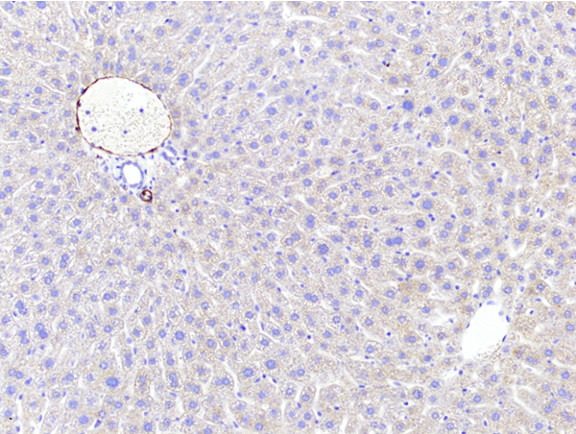

Figure 6: Histopathology for C57BL/6NTac mice placed on D09100310 diet (MASH B6NTac) or kept on chow diet (Control B6NTac) from 6 weeks of age. Animals were on diet for 27, 35 or 53 weeks. Hematoxylin and eosin (H&E) staining illustrates morphological changes including steatosis and infiltration of immune cells. Activated HSCs were identified in liver sections by using a rabbit polyclonal antibody to alpha-smooth muscle actin (a-SMA) (1:500 dilution; ab5694; Abcam, Cambridge, MA) which was detected by an anti-rabbit IgG embedded polymer with embedded horseradish peroxidase and visualized with 3,3′-diaminobenzidine (DAB) chromogen (Agilent, Carpentaria, CA). Hepatocellular lipid droplets were identified by visualization of the lipid-binding protein adipophilin known to be expressed in steatotic livers. Sections of livers were probed using a rabbit polyclonal anti-adipophilin antibody (1:200 dilution; NB110-40877, Novus Biologics, Littleton, CO) which was detected by an anti-rabbit IgG embedded polymer with embedded horseradish peroxidase and visualized with 3,3′-diaminobenzidine (DAB) chromogen (Aligent, Carpentaria, CA). Picrosirius red (PSR) staining illustrates collagen I and III fibers and is used to measure fibrosis. The same individual MASH or control animal is shown for all four stains in a particular time point. Different individual animals were used for each time point (i.e. data is not longitudinal by animal). Histopathology services provided by IDEXX BioAnalytics.